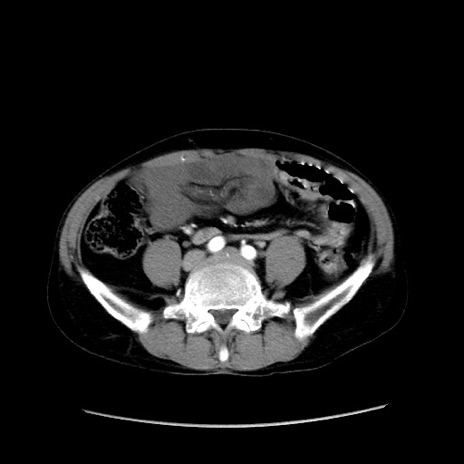

症例37(横断像)

【症例】40歳代 男性

【主訴】腹痛

【現病歴】4時間ほど前に電車に乗車中に臍部上より腹痛出現。徐々に増悪し起立困難となり、救急外来受診。生ものは数日食べていない。今朝お雑煮を食べた。

【身体所見】BT 36.8℃、BP 117/84mmHg、HR 91/min、SpO2 97%、苦悶様、腹部:臍上部広範囲圧痛あり、反跳痛±

【データ】WBC 8100、CRP 0.03